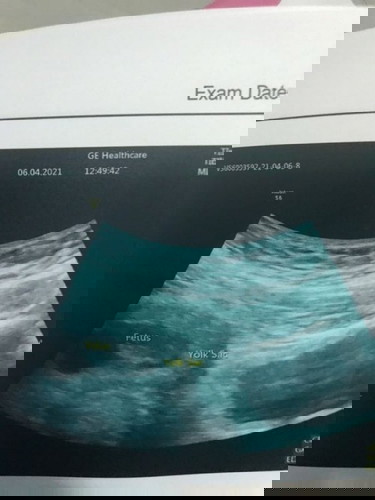

เป็นค่ะ หมอฉีดยากันแท้งให้ และให้ยามากินด้วยค่ะ อัลตร้าซาวด์ไปหมอแจ้งว่าน้องปกติดี หัวใจเต้นปกติ ตอนนี้ 7w ค่ะ วันที่ 23/4/64 หมอนัดตรวจ ค่ะ